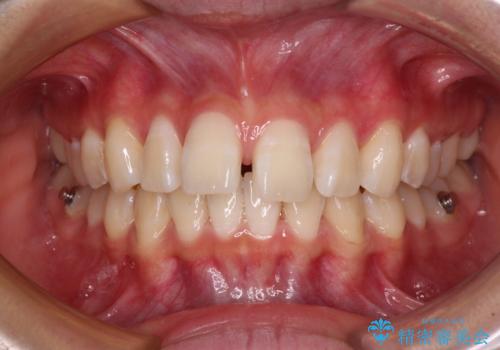

深い咬み合わせで前方に煽られた前歯 高校生のインビザライン矯正治療

- 前歯の隙間と前方に飛び出していることを気にして来院された患者様です。

奥歯の咬み合わせを見ると、上顎が下顎に対して相対的に前方にありました。

咬み合わせも深くなっていたため、上顎臼歯を後方に移動させつつ、下顎の小臼歯を直立させ、奥歯の咬み合わせを改善する必要があります。

奥歯の咬み合わせと深い咬み合わせを改善した後、隙間などをインビザラインで整えることとしました。

インビザラインをしっかりと装着したことはもちろん、高校生は歯の動きが早いため、非常に短期間で治療を終えることができました。